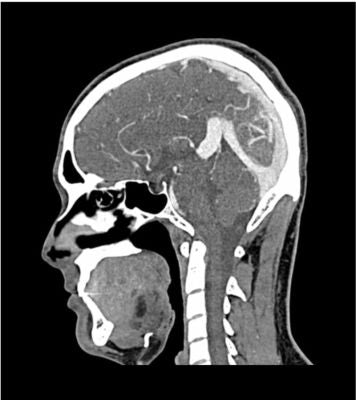

Description

This phantom simulates a contrast medium-enhanced head in the arterial phase (CT angiography). It covers the vertex to the fifth cervical vertebra. The right hemisphere has an arteriovenous malformation.

The phantom can be used in CT (including CBCT) to evaluate and optimize imaging performance and AI-enabled diagnosis. It is also suited for training purposes.